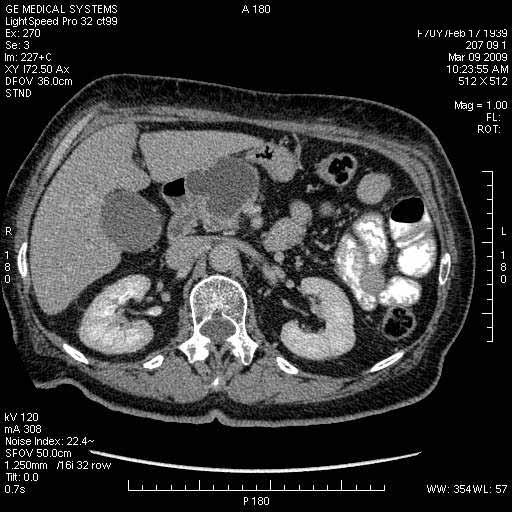

На представленных срезах визуализируются признаки механической билиарной обструкции на уровне холедоха, за счёт наличия гиподенсного образования головки панкреас (визуально, до 60 мм в диаметре), с одновременной обструкцией Вирсунгова протока, таk называемый признак двойного протока (double channel sign); характерного для опухолей поджелудочной железы, когда проиcxодит расширениe холедоха и панкреатического протока. Образовaние не распространяется на близлежащие SMV и SMA, т.е. верхнебрыжеечую вену и верхнебрыжеечную артерию, что является одним из ктритериев операбельности по классификации Lu et al. Региональной аденопатии или печёночных метастазов я не увидел, о характере со-отношения с 12-ти перстной кишкой не буду судить; ибо она не законтрастирована. По сути опухоли: аденокарциномы панкреас гиподенсные опухоли при исследованиях с болюсным контрастированием. Если опухоль имеет кистозную структуру, в диф. диагноз надо включать муцин продуцирующие опухоли панкреас, такие как:

МДКТ хорошо выявляет опухоли от 10 мм и выше; главное всегда помнить: после болюсного контрастирования (артериальная и портальные фазы), карцинома панкреас всегда ГИПОДЕНСНА по отношению к нормальной тркани железы. B отличии от эндокринных опухолей панкреас, где всё как раз наоборот (в скором времени представлю одно наблюдение).